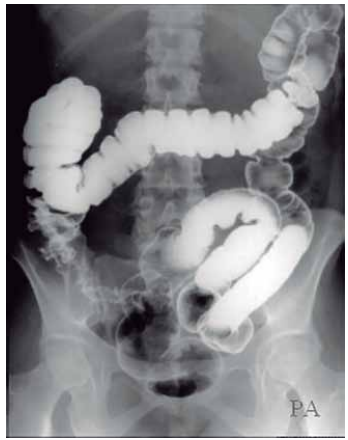

Observe a figura a seguir:

O duplo contraste no exame contrastado do sistema digestório, enema opaco, contempla a visualização do intestino grosso.

Assinale a alternativa que denomina, corretamente, a sequência da sua divisão.